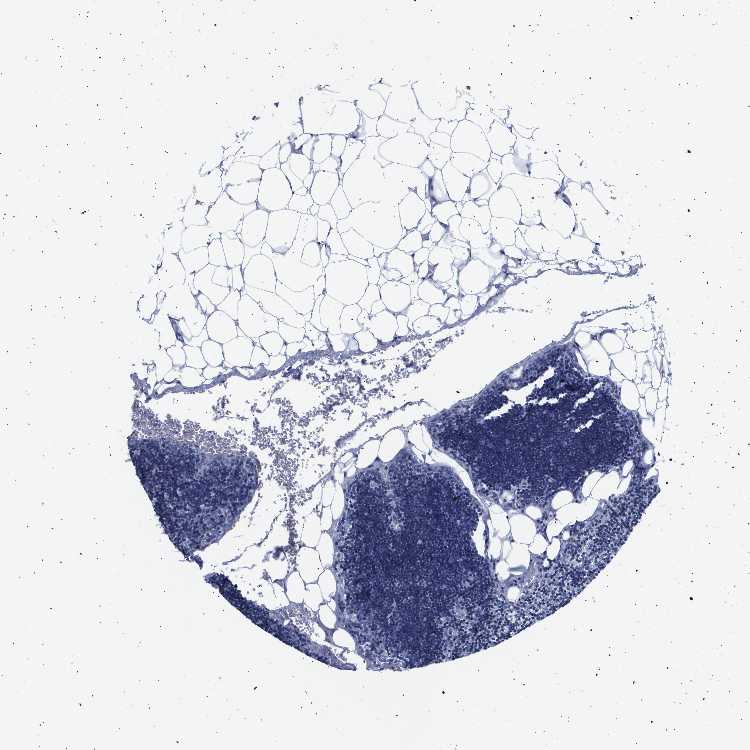

LYMPH NODE - Antibody stainingi

Antibody staining in the annotated cell types in the current human tissue is reported as not detected, low, medium, or high, based on conventional immunohistochemistry profiling in selected tissues. This score is based on the combination of the staining intensity and fraction of stained cells.

Each image is clickable and will lead to virtual microscopy that enables deeper exploration of all samples and also displays staining intensity scores, fraction scores and subcellular localization as well as patient and tissue information for each sample.

Antibody HPA017955

Germinal center cells Not detected

Non-germinal center cells Not detected